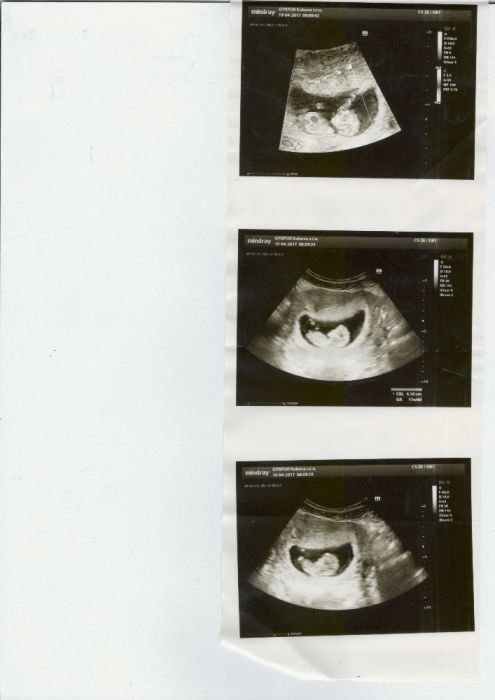

ahoj holky, gratuluji k dobrým zpravam z ultrazvuku. Take jsem dnes byla na kontrole, dle ultrazvuku 8tt, srdíčko bylo videt:) a možná dokonce 2, ale to si na potvrzeni musím 14 dni počkat dnes si nebyla jista, ale možná jsou 2 zasebou. Ted tu informaci musím zpracovat :D

Bluumy,to je krasna zprava a jeste krasnejsi fotka.Bobisci malinkati,krasni...jsem dojata z mizejiciho dvojcatka,co si svoje misto na tomto svete chce vybojovat!

Blummy a Terezko, super to je uzasne, moc gratuluju!!!:) Blummy foteky je krásná♥ taky Vám posílám na pokoukání :)

Ahoj holky, tak se jdu také pochlubit :) dnes kontrola 11tt, odběry krve, měření pánve atd. Konečně jsem dostala prukazku, mám hroznou radost, že je mimi v pořádku a na UTZ už taky vypadá jako malej človíček. Měla jsem strach, jsem teď hrozně nachcípaná, nedokážu vůbec fungovat. 3.5. jdeme na genetiku, tak se s přítelem strašně těšíme co uvidíme :) Přikládám také foto z dneška